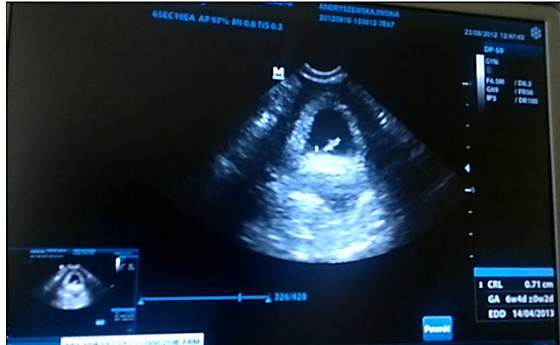

Nie bylo mnie przez dwa dni a tu tyle sie nadzialo. Gratuluje wam wszystkim udanych wizyt. Ja wczoraj tez zaliczylam swoja i moj babelek ma 7mm wielkosci i serduszko wali jak szalone. Termin na 14 Kwietnia. Jedyna zla wiesc to taka ze moje wyniki tarczycowe TSH sa duzo za duze i musze brac hormony aby to zanizyc do bezpiecznego stanu.